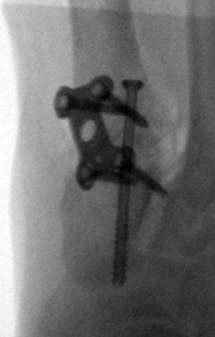

Es wird hier die Lapidusarthrodese mit Fixation durch eine medial angebrachte winkelstabile Platte in Kombination mit einer Zugschraube beschrieben 2. Durch diese Kombination läßt sich eine verglichen zur Schraubenosteosynthese hohe Primärstabilität erreichen, verbunden mit einem niedrigen Risiko einer Pseudarthrosenbildung 3.

Im Vergleich zur reinen Schraubenosteosynthese höhere Primärstabilität und geringere Pseudarthroserate 45.

Bei Verwendung von modernen winkelstabilen Implantaten hohe Primärstabilität ohne Korrekturverlust mit der Möglichkeit eines frühzeitigen Belastungsaufbaus 7.

Die Lapidusarthrodese ist ein potentes Verfahren zur Korrektur des mittleren und ausgeprägten Hallux valgus. Viele Implantatehersteller bieten mittlerweile zur Stabilisierung der Lapidusarthrodese die Möglichkeit einer plantaren Plattenosteosynthese an 12. Die biomechanischen Vorteile einer plantaren Plattenpositionierung liegen auf der Hand, jedoch ist das Operationstrauma für die plantare Plattenanlage größer und der Eingriff technisch schwieriger. Die mediale Plattenanlage ist ein seit vielen Jahren etabliertes Verfahren, wobei aus unserer Erfahrung die theoretischen Nachteile der subkutan liegenden Platte und die geringere Primärstabilität verglichen zur plantaren Platte im Alltag wenig ins Gewicht fallen – verglichen zu der bei medialer Plattenanlage einfacheren OP Technik. In der Literatur werden für die mediale Plattenanlage mit Kompressionsschraube gute Ergebnisse berichtet. Cottom et al. 5 berichten über eine Pseudarthroserate von 2%, allerdings war in 17% der Patienten eine Metallentfernung notwendig. Menke et al. 16 berichteten über 8% Pseudarthrosen. Alle Autoren berichten über eine sehr gute Korrektur des Intermetatarsalwinkels. Die mediale Plattenosteosynthese mit Kompressionsschraube ist ein etabliertes Verfahren zur Osteosynthese des Tarsometatarsale-I-Gelenks. Die Primärstabilität liegt signifikant höher als bei der Schraubenosteosynthese, was einen stufenweisen postoperativen Belastungsaufbau erlaubt. Das Operationsverfahren ist technisch weniger anspruchsvoll als die plantare Plattenosteosynthese, was vor allem dem weniger routinierten Operateur zu Gute kommen dürfte. Die Notwendigkeit zur Metallentfernung ergibt sich in bis zu 20% der Patienten.